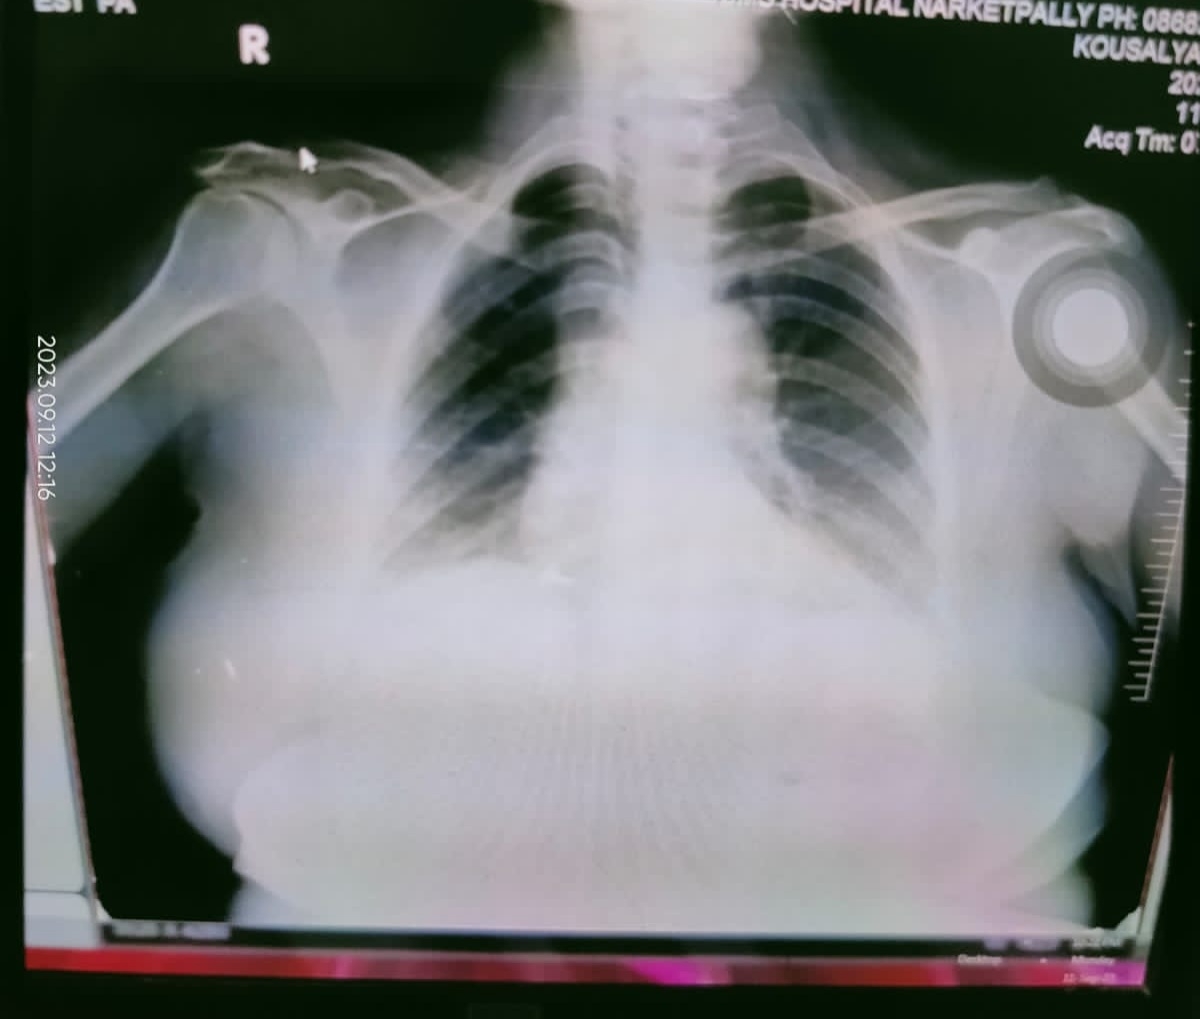

X -ray: